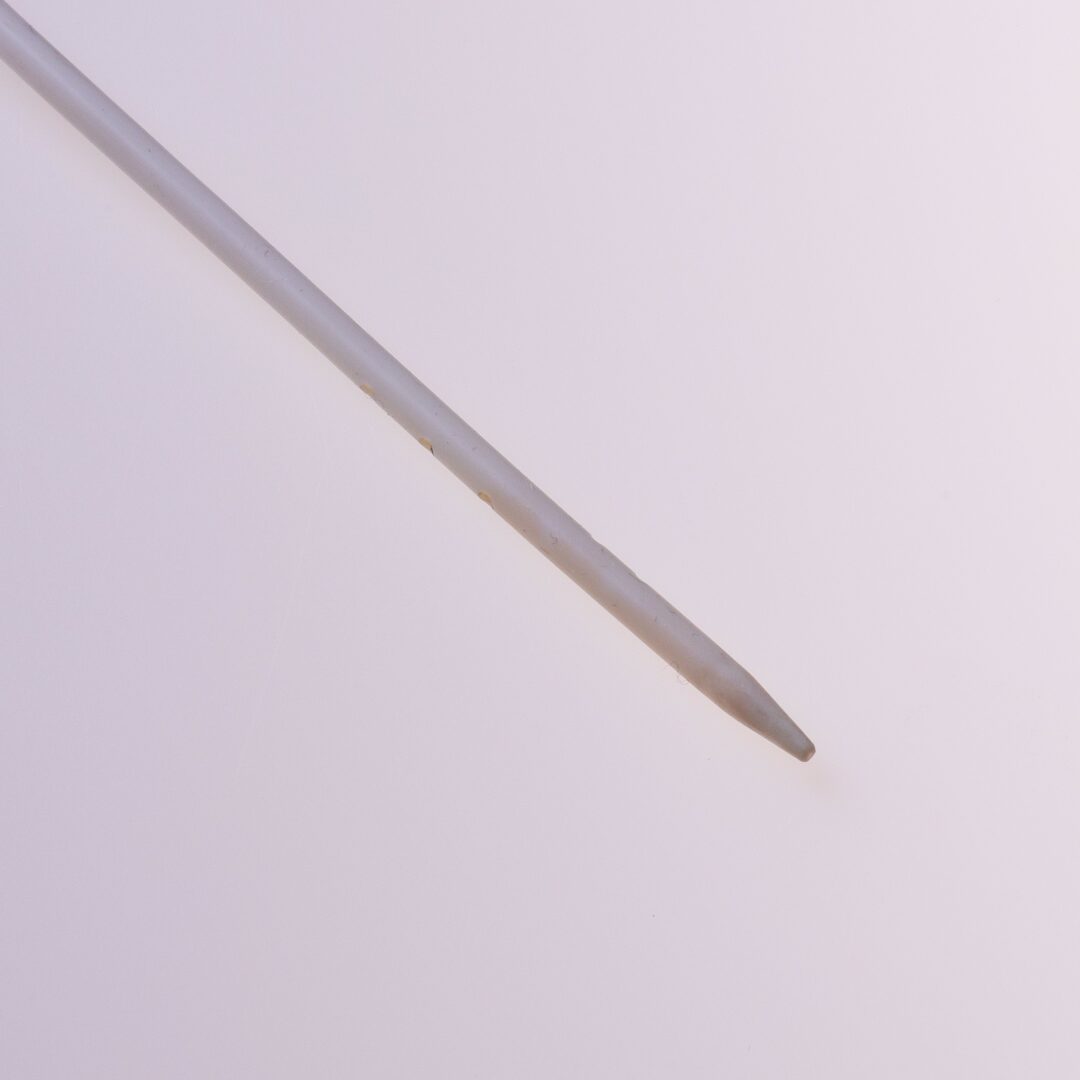

Tip Design

Der Softline® verfügt über ein konisches Spitzendesign und weist einen Lumendurchmesser von 7 French oder 9 French auf.